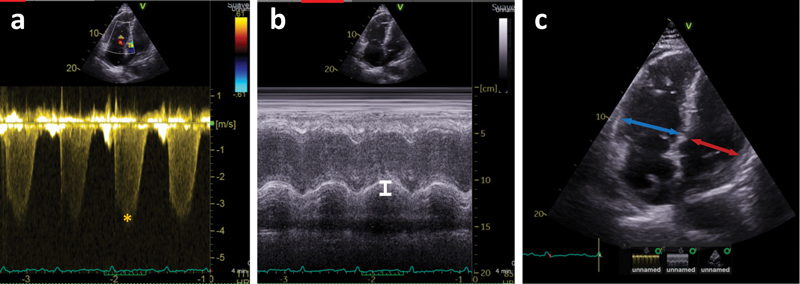

背景 在急性肺栓塞(PE)患者中,超声心动图对右心室(RV)功能障碍的鉴定将为预后判断和临床决策提供依据。肺栓塞信息登记处(RIETE)是世界上最大的客观确诊肺栓塞患者登记处。现场报告的 RV 超声心动图测量结果的可靠性尚不清楚。我们旨在验证 RIETE 登记处报告的关键 RV 超声心动图测量结果。方法 随机抽取 51 例因急性 PE 而接受经胸超声心动图(TTE)检查的 RIETE 患者。由两名独立观察员组成的核心实验室对经胸超声心动图进行了去身份化分析,并对现场报告的数据进行了盲法处理。为了研究可靠性,在两名观察者之间以及两名观察者的平均值与 RIETE 现场报告数据之间获得了类内相关系数 (ICC) 和 Bland-Altman 图。结果 核心实验室观察者之间的差异非常有限,所有 TTE 参数的相关系数均大于 0.8。在三尖瓣环面收缩期偏移(ICC 0.728;95% 置信区间 [CI],0.594-0.862)和肺动脉收缩压(ICC 0.726;95% 置信区间 [CI],0.601-0.852)等关键参数上,核心实验室观察员与现场报告数据的一致性非常高。右心室与左心室直径比值(ICC 0.739;95% CI,0.443-1.000)的一致性得到了验证,但缺失数据限制了估计值的精确度。Bland-Altman图显示差异接近于零。结论 我们在 RIETE 登记中显示了关键 RV 现场报告测量值的高度可靠性。确定这些数据的有效性可增加后续调查的信心和可靠性。

Background  In acute pulmonary embolism (PE), echocardiographic identification of right ventricular (RV) dysfunction will inform prognostication and clinical decision-making. Registro Informatizado Enfermedad TromboEmbolica (RIETE) is the world's largest registry of patients with objectively confirmed PE. The reliability of site-reported RV echocardiographic measurements is unknown. We aimed to validate site-reported key RV echocardiographic measurements in the RIETE registry. Methods  Fifty-one randomly chosen patients in RIETE who had transthoracic echocardiogram (TTE) performed for acute PE were included. TTEs were de-identified and analyzed by a core laboratory of two independent observers blinded to site-reported data. To investigate reliability, intraclass correlation coefficients (ICCs) and Bland-Altman plots between the two observers, and between an average of the two observers and the RIETE site-reported data were obtained. Results  Core laboratory interobserver variations were very limited with correlation coefficients >0.8 for all TTE parameters. Agreement was substantial between core laboratory observers and site-reported data for key parameters including tricuspid annular plane systolic excursion (ICC 0.728; 95% confidence interval [CI], 0.594-0.862) and pulmonary arterial systolic pressure (ICC 0.726; 95% CI, 0.601-0.852). Agreement on right-to-left ventricular diameter ratio (ICC 0.739; 95% CI, 0.443-1.000) was validated, although missing data limited the precision of the estimates. Bland-Altman plots showed differences close to zero. Conclusion  We showed substantial reliability of key RV site-reported measurements in the RIETE registry. Ascertaining the validity of such data adds confidence and reliability for subsequent investigations.